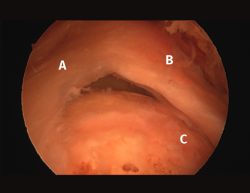

Figura 4. Rotura de supra- e infraespinoso en forma de L invertida con presencia de 2 capas. A: tendón supraespinoso; B: tendón infraespinoso; C: cabeza humeral.

Figura 5. Rotura de tipo C1. A: rotura pequeña de espesor completo del supraespinoso; B: cabeza humeral.

Sin embargo, las clasificaciones basadas en el tamaño de la rotura deben ser bidimensionales, ya que la visión unidimensional puede ser engañosa, al mostrar el tamaño de la rotura solo desde el plano anteroposterior(4). Por esta razón, proponemos el sistema de clasificación del manguito posterosuperior sugerida por Snyder, que aporta información no solo del tamaño, sino del número de tendones afectados y la presencia de tejido cicatricial(7). En las lesiones de tipo C1 la lesión atraviesa todo el espesor del tendón y en el eje transversal es pequeña y punzante (Figura 5). Las de tipo C2 son roturas de espesor completo pero la distancia entre los extremos de la rotura es menor de 2 cm con escasa retracción (Figura 6). En las de tipo C3 la rotura afecta en sentido transversal entre 3 y 4 cm con mayor retracción implicando 2 tendones (Figura 7). Y las de tipo C4 son la rotura masiva del manguito de los rotadores con una afectación de espesor completo de toda la anchura de 2 o más tendones asociando importante retracción (Figura 8).